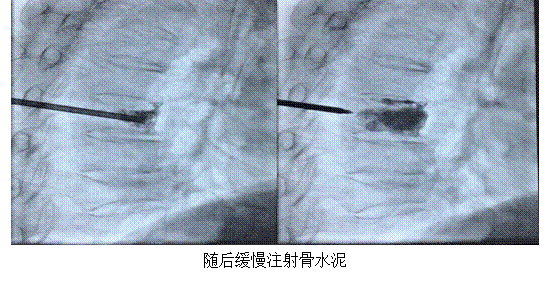

骨轉(zhuǎn)移瘤是惡性腫瘤的常見(jiàn)并發(fā)癥,其中脊柱轉(zhuǎn)移瘤發(fā)生率可高達(dá)30%~50%。最易發(fā)生脊柱轉(zhuǎn)移的腫瘤包括肝癌、乳腺癌、肺癌、前列腺癌等。脊柱轉(zhuǎn)移瘤嚴(yán)重影響患者生活治療,其主要表現(xiàn)為難以忍受的疼痛、病理性骨折、神經(jīng)根或脊髓壓迫癥狀,嚴(yán)重時(shí)會(huì)導(dǎo)致患者癱瘓。經(jīng)皮椎體成形術(shù)(Percutaneous Vertebroplasty,PVP),也叫經(jīng)皮骨水泥成形術(shù),是由 Deramond和Galibert兩位學(xué)者首次提出,其原理是在高清晰度影像設(shè)備導(dǎo)引下用骨穿針經(jīng)皮通過(guò)椎弓根或椎弓根外側(cè),實(shí)時(shí)透視下向病變椎體內(nèi)注入聚甲基丙烯酸甲酯 (PMMA),以達(dá)到提高脊柱穩(wěn)定性、恢復(fù)并增加椎體力學(xué)強(qiáng)度和剛度的目的。

目前經(jīng)皮椎體成形術(shù)廣泛應(yīng)用于椎體壓縮性骨折、骨轉(zhuǎn)移性腫瘤患者,在患者病變椎體內(nèi)注射PMMA后,可以恢復(fù)脊柱形態(tài),同時(shí)其放熱效應(yīng)可殺死腫瘤組織并破壞周圍神經(jīng),達(dá)到穩(wěn)定椎體形態(tài)及緩解疼痛的作用。椎體轉(zhuǎn)移性骨腫瘤患者和椎體骨折行PVP可立即緩解疼痛,同時(shí)增加了椎體強(qiáng)度,具有防止病理性骨折、改善腫瘤患者生活質(zhì)量和延長(zhǎng)患者生存時(shí)間的作用。